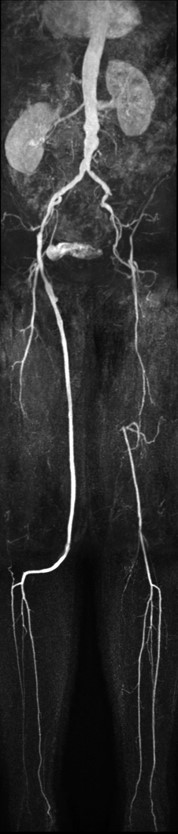

MR Angiography (run-off)

Utrecht Medical Center, The Netherlands